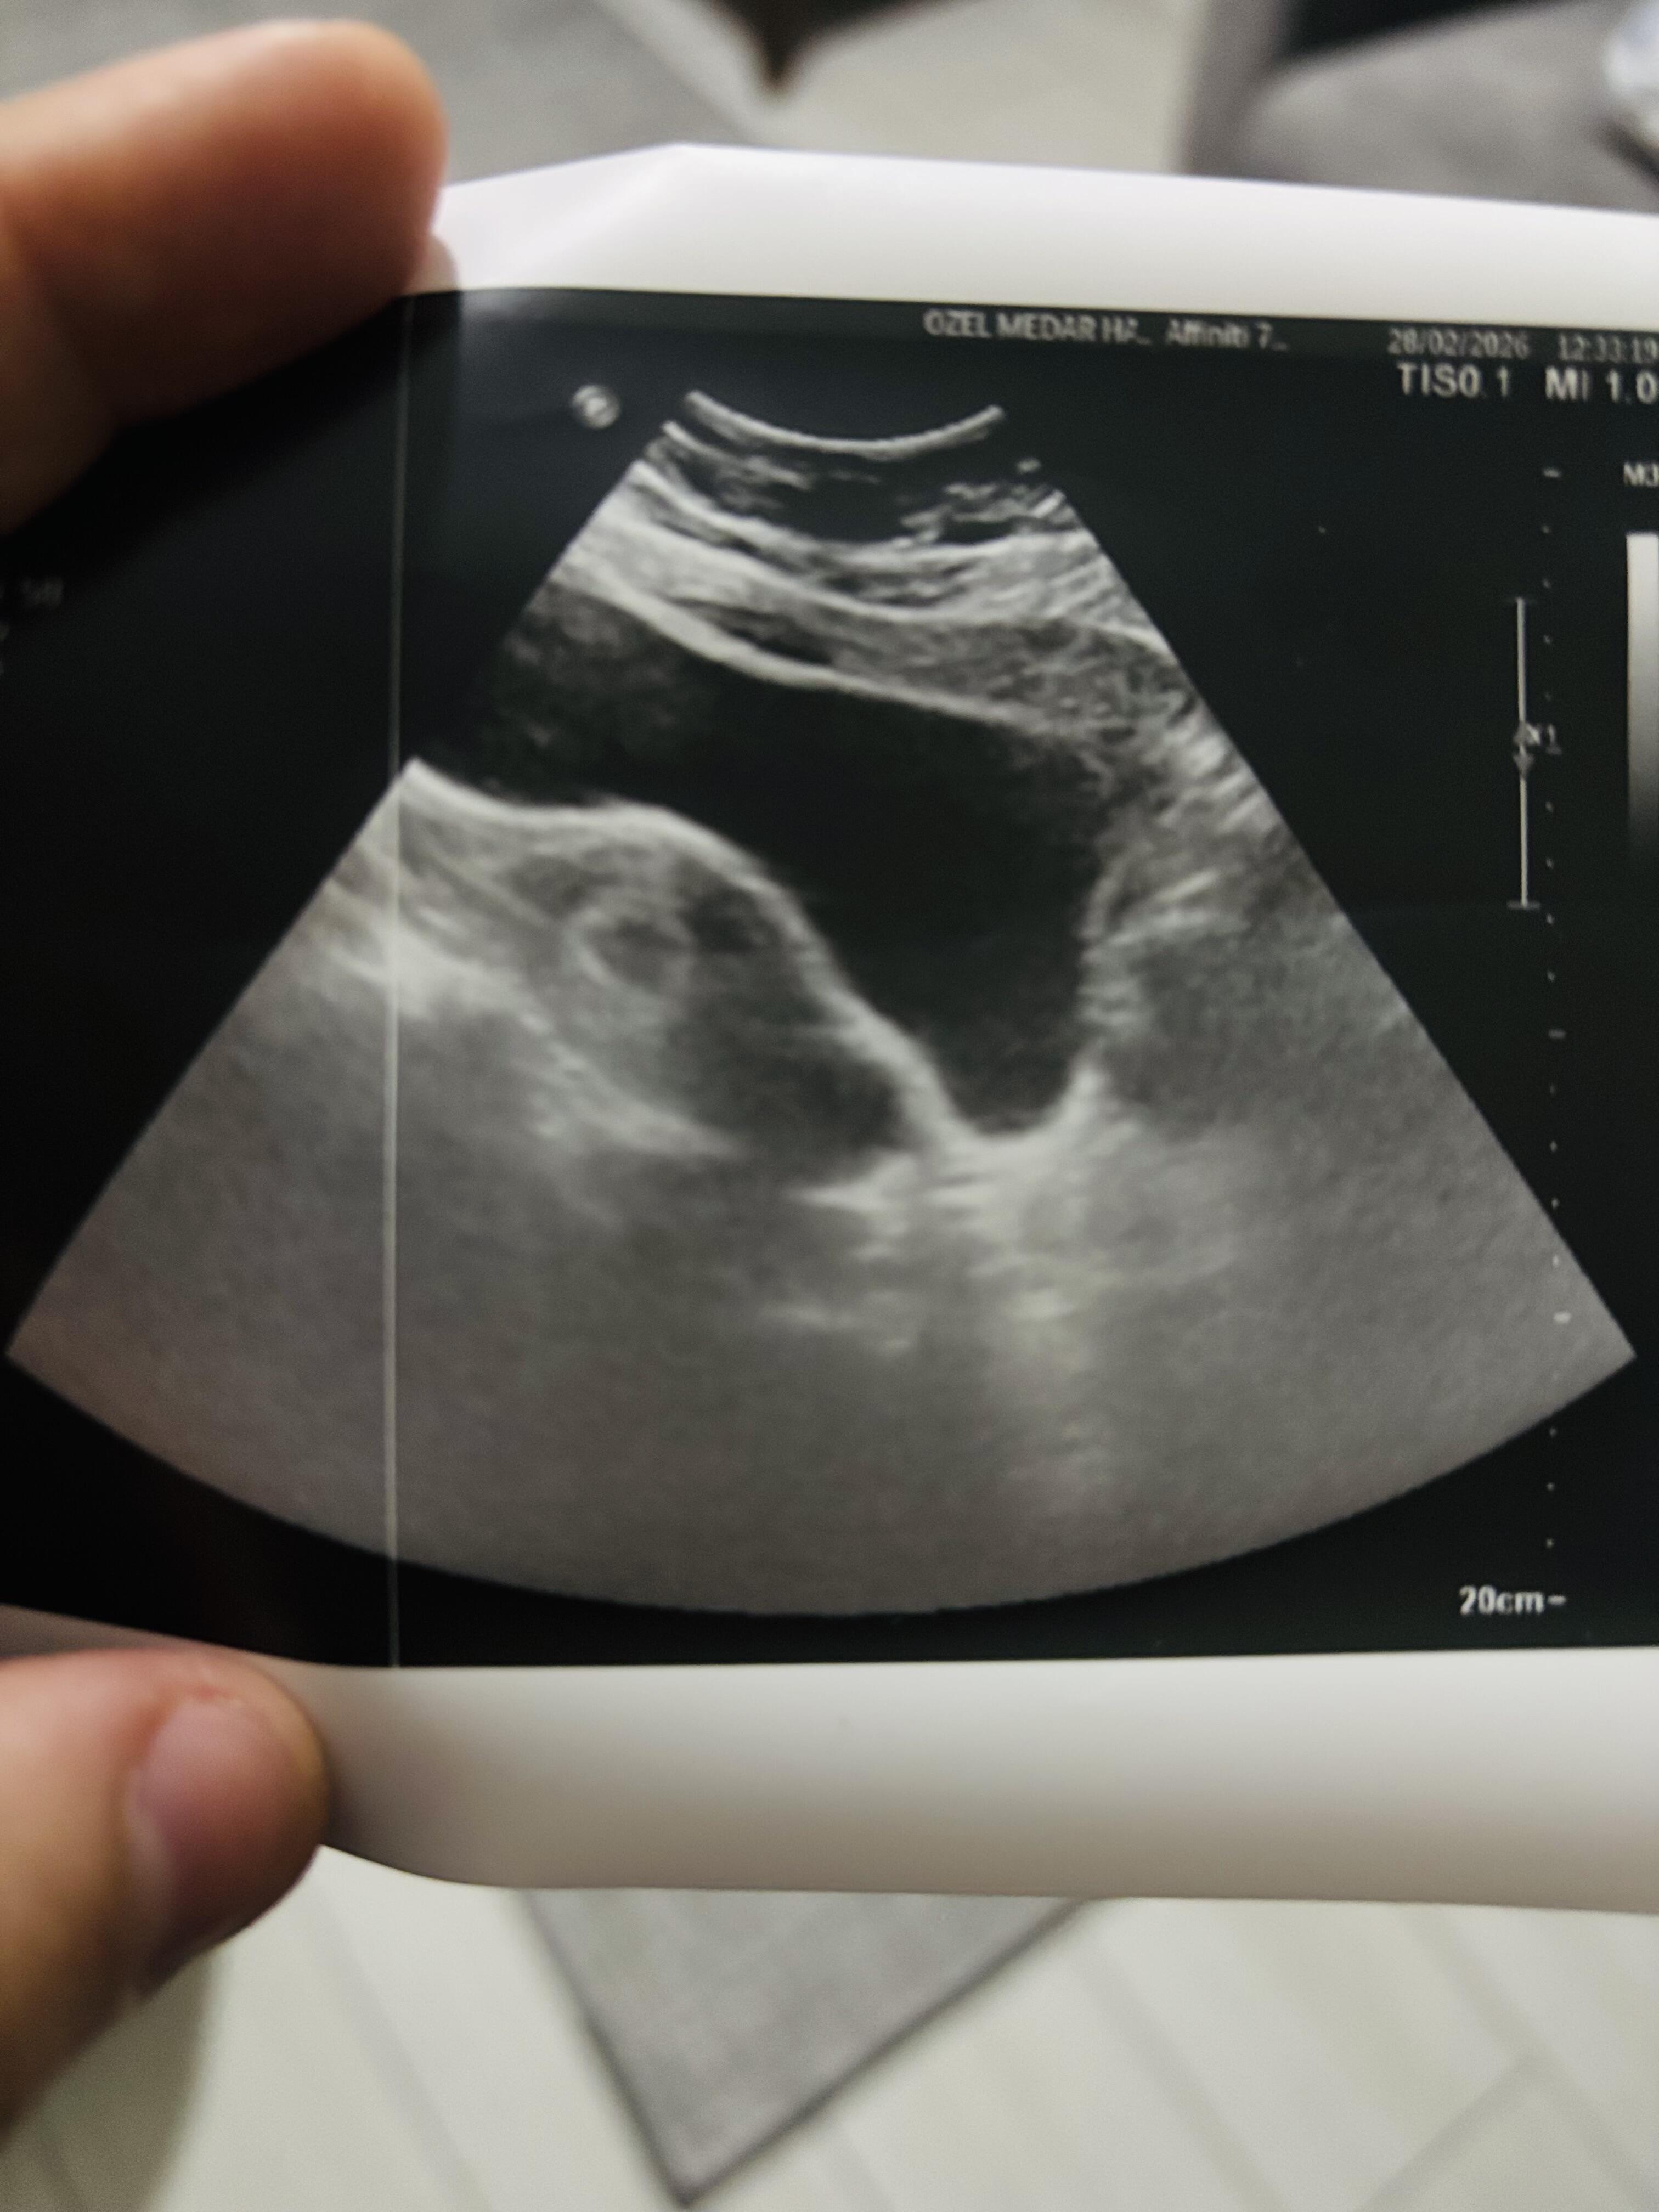

Çok anlamam ama sanırım senin isaretlediklerin bebekle alakalı hicbirsey o siyah yerin içinde embriyo olusucak sonrasinda yolk falan daha net gözükür benim attığım resimde 7haftalik falandı düşün nokta şeklindeydi biraz sabret sağlıkla Güzel haberler alırsın inşallah ilerleyen haftalarda çok erken gitmissin doktora ![]()

Şuan 35haftaligiz biz çok şükür

ben örnek olsun diye eski fotoraf atmistim